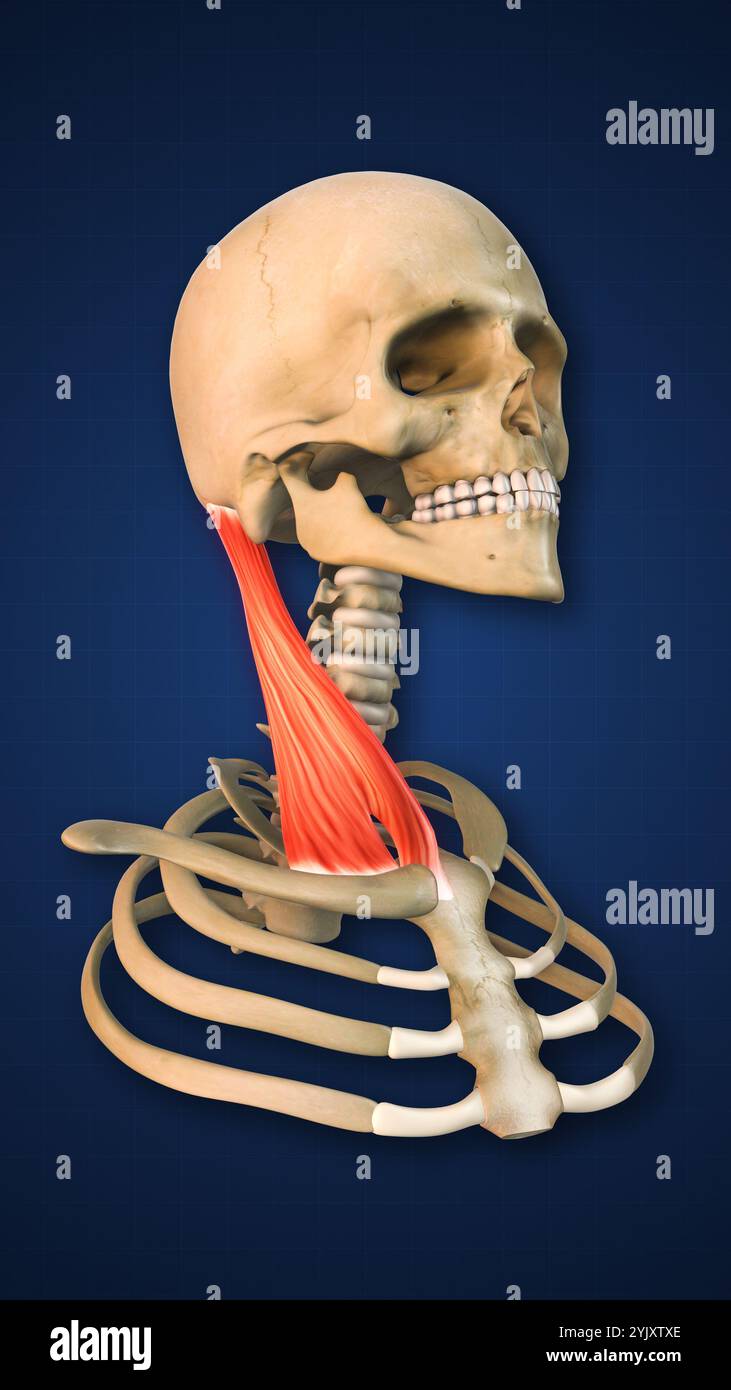

RMJE7CWP–Der Plexus brachialis ist ein Nervennetz im Nacken- und Schulterbereich, das für die motorischen und sensorischen Funktionen der oberen Extremität von wesentlicher Bedeutung ist. Das Bild zeigt den Plexus brachialis an seiner anatomischen Position.